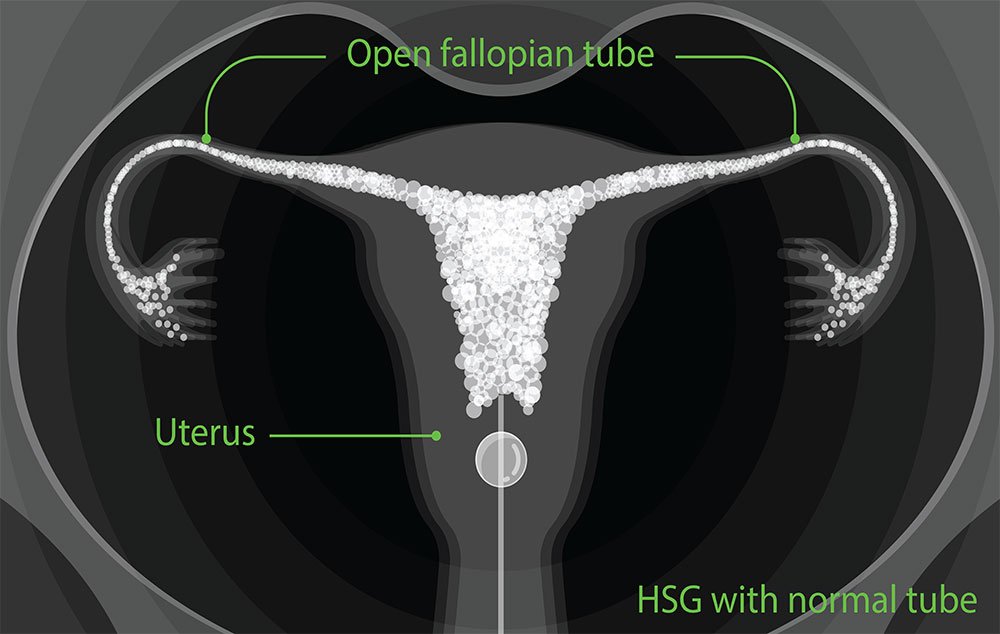

High-resolution digital imaging for detailed cellular analysis.